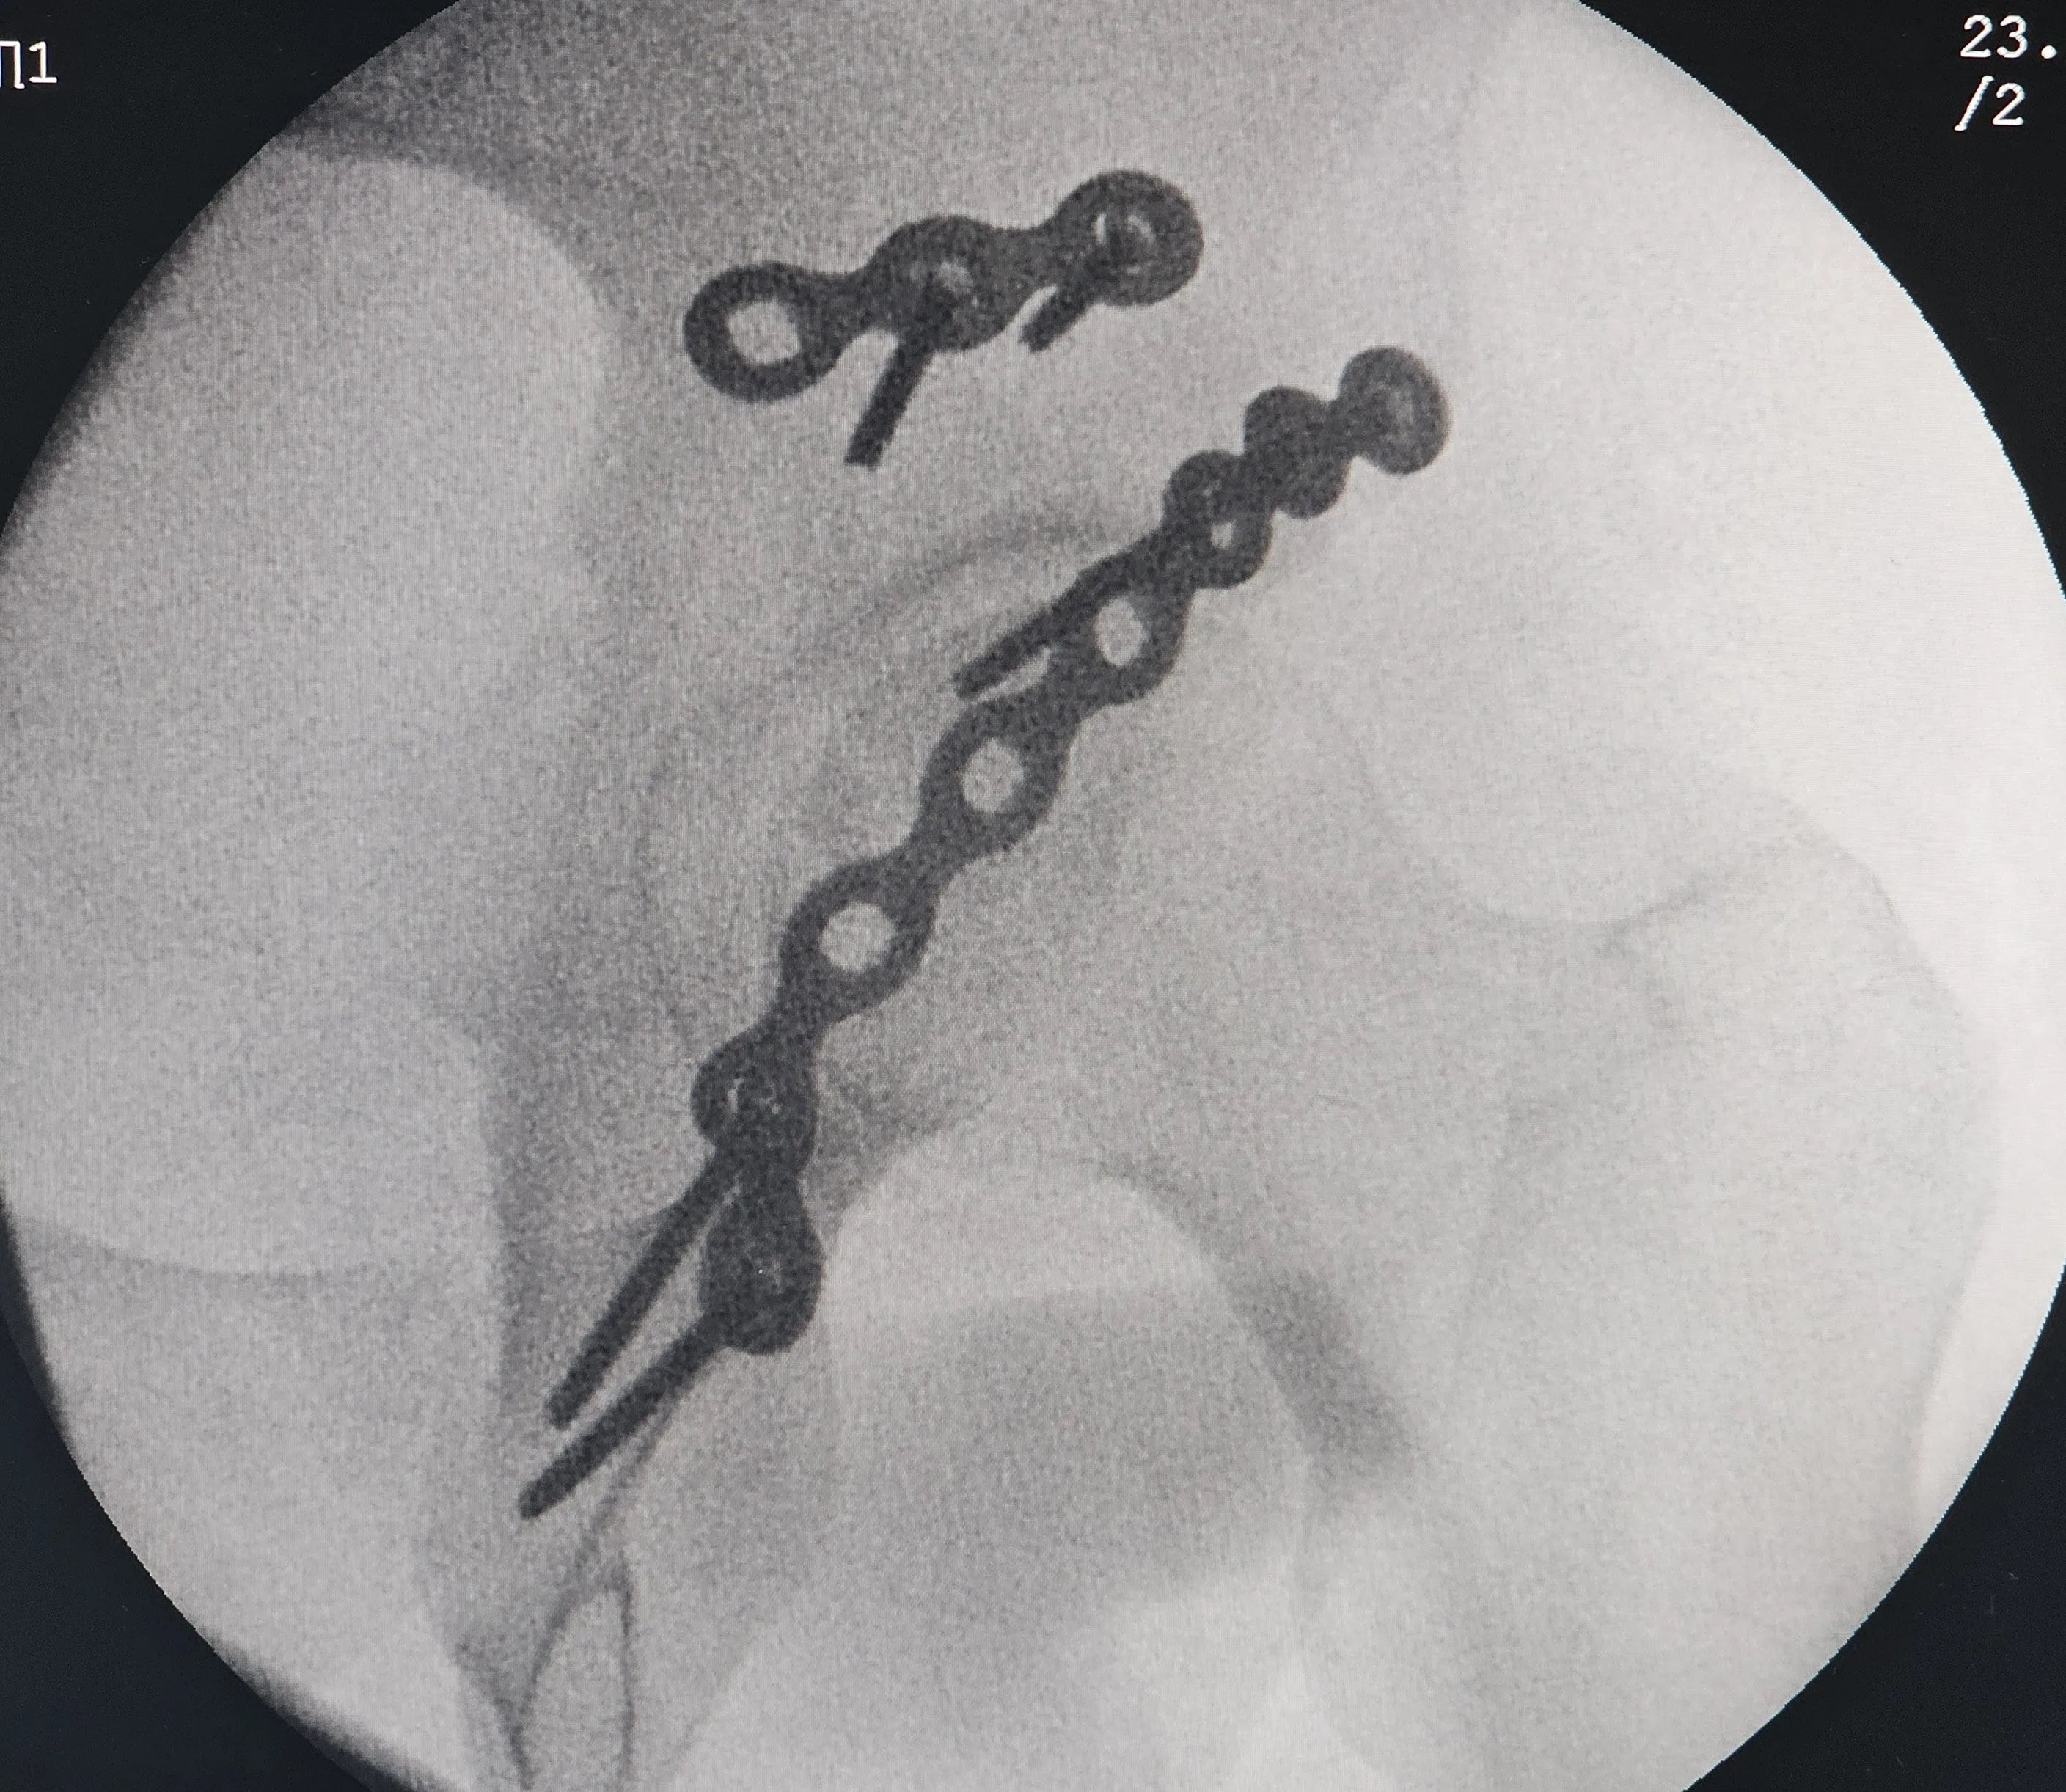

- Fixação Definitiva com Múltiplas Placas: Aprenda a fixar a placa principal no ísquio, contornando todo o rebordo posterior, com parafusos direcionados para o teto acetabular. Utilize uma segunda placa no vértice do fragmento superior para fixação. Compreenda como a utilização dessas duas placas proporciona redução e estabilidade satisfatórias, eliminando a necessidade de placas em mola.